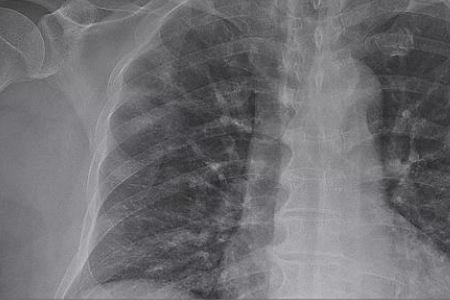

目前全世界有几十个国家确诊了新型冠状病毒感染的肺炎病例,其中意大利国家最为严重,法国的疫情也不容乐观,目前确诊病例增至1784例,另外,死亡病例增至33例。对此,如果你对法国最新疫情感兴趣的话,建议往下看看更为详细的内容。

法国新冠肺炎确诊病例当地时间10日仍在持续激增,达到1784例,死亡病例增至33例。法国总统马克龙强调欧盟协调应对疫情。

法国卫生总署署长萨洛蒙在当晚的记者会上说,法国10日确诊病例数为372例,重症病例增至86例。他说,虽然绝大多数新冠肺炎患者可以痊愈,但要做好对年老体弱者的保护。萨洛蒙总结了法国的33例死亡病例的年龄分布情况。他说,死亡患者中有23人的年龄超过了75岁,65岁到74岁年龄组的人有4位,年龄在64岁以下的死亡患者有5位。死亡患者中没有未成年人。(备注:信息来源“中国新闻网”。)